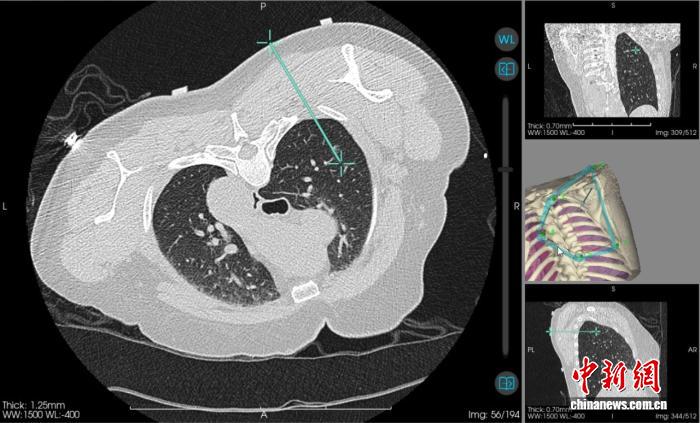

当天,该院心胸外科主任阳诺带领消融团队开展手术。他介绍,在术前,穿刺手术机器人系统基于患者CT影像,能自动构建详细的肺部3D立体模型,清晰呈现结节与周围血管、气管等重要组织的位置关系。

“它就像一位‘智能导航员’,精准规划穿刺路径、角度与深度,有效避开血管、气管等重要组织结构,将误差控制在毫米级。”阳诺说。

术中,机器人就像有了“智慧眼睛”和“稳定双手”,整个过程机械臂平稳导航,无需调针,实现对靶病灶的“一针到位”,减少了CT扫描次数和患者的辐射暴露。机器人的应用避免了人为因素可能带来的穿刺偏差,从而减少对周围正常组织的损伤,降低了气胸、出血等并发症的发生率,也缩短了手术时间。